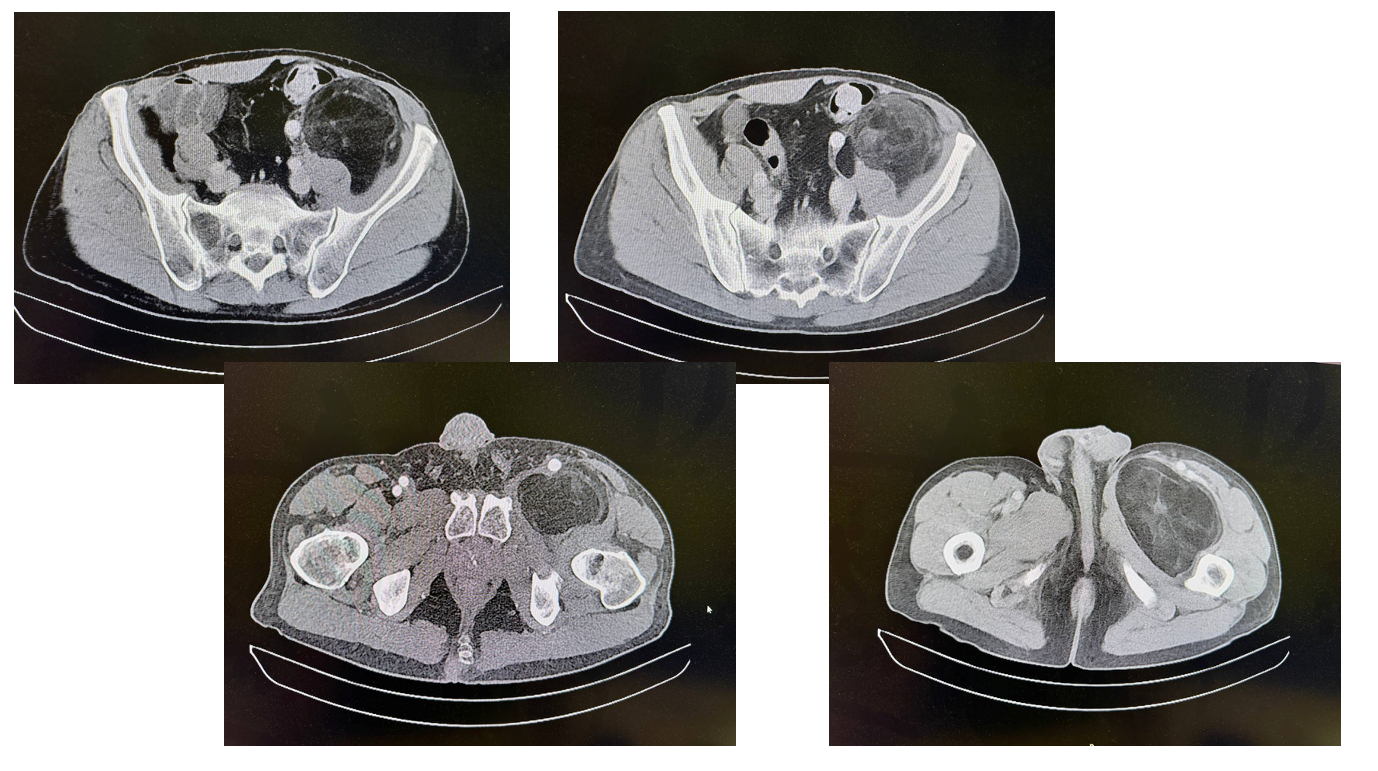

МРТ от 30.12.2025: Крупное объемное образование полости таза, левой паховой области и в/3 бедра, с преимущественным содержанием в структуре жировой ткани.

КТ с в/в контрастированием + режим ангиографии